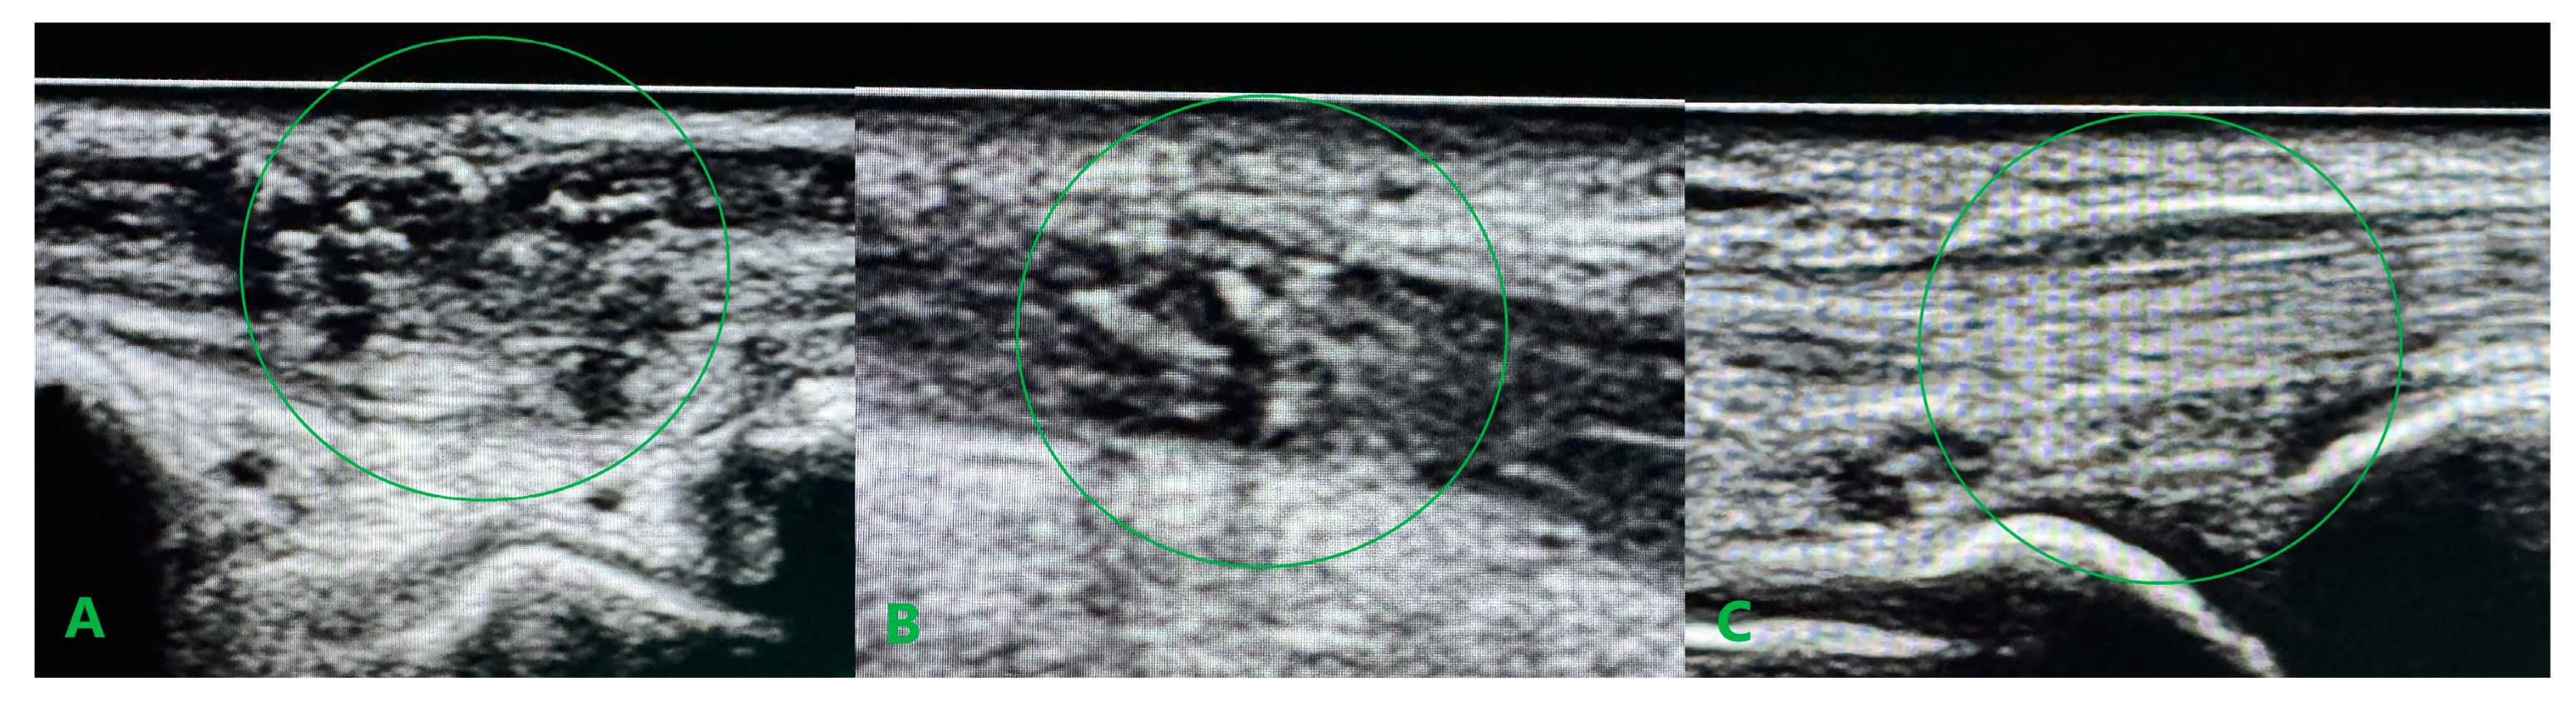

Longitudinal ultrasound sections of the reconstructed tendons six weeks after surgery confirming the efficacy of the distal Pulvertaft sutures. APL (A), ECRL (B), and ECRB (C). The most suitable ultrasound graft integration for ECRB tendon.

In our case, the repair of the damaged retinaculum consisted of creating two separate canals in the surrounding scar tissue at the spot of the second and third anatomical compartments to ensure good graft adhesion without conflict during sliding motion. This approach stays in line with Kawakatsu M. et al. reports, which emphasized that it is important to reconstruct only the extensor retinaculum, not the entire sliding surface [10]. Unlike the case described by the above authors, our patient did not require further tenolysis, probably because we introduced gentle passive movements from the third week after surgery. We avoided the necessity to release adhesions, which can also be explained by the fact that intraoperatively, during radical passive flexion and extension of the hand at the level of the reconstructed retinaculum, only the PL graft was sliding beneath without conflict with the level of suturing. A considerable issue during tendon reconstructive procedures is determining the appropriate graft tension. In the case of isolated extensor reconstruction, techniques for estimating graft tension are known, such as those described by Kamoi F. et al., who treated 20 patients with EPL damage with good results [11]. They assumed that the tension of the reconstructed EPL should be adjusted so that the center of the distal edge of the thumbnail is elevated 2 cm above the operation table. The situation is much more complex in the case of multiple tendon reconstruction. In our patient, the tension of the ECRB and ECRL grafts was determined to achieve a neutral hand position in both the flexion/extension and the ulnar/radial deviation plane. The tension of the APL graft was an intraoperative dilemma, which was sewn in with minimal tension, not guided by the position of the thumb. This may translate into afterward problems with rehabilitation in thumb opposition. Postoperative rehabilitation for extensor tendon damage in zones V to VII has historically relied on the immobilization of the hand for 4 to 6 weeks after surgery. From the literature, in zones V to VII, complications can arise with tendon adhesions, joint contracture, prolonged rehabilitation, and limitations of hand function. Extensor tendon rehabilitation providing passive or dynamically assisted sliding of the reconstructed tendon, the same as an actively mediated extension, significantly improves the quality of results compared to static splinting [8,12,13,14]. In our case, the introduction of the passive wrist and hand movements from the third week after surgery assisted active extension from the fifth week after surgery, and the patient’s involvement in the rehabilitation process resulted in a very good functional outcome. Ultrasound examination (UE) should focus on assessing early results and detecting complications, mainly tendon adhesions. UE also allows for managing rehabilitation progress and assessing the sliding movement of the repaired tendon or tendon graft. In our case, UE was used to confirm the sliding movement of the PL grafts during passive extension movements at the early rehabilitation stage and to exclude splitting of the tendon ends.